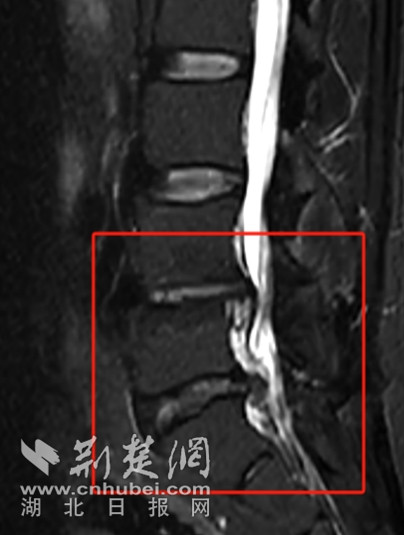

入院后,急诊科医生迅速为余先生完善了一系列相关检查。磁共振结果显示余先生患有一系列腰椎问题,最终被诊断为腰椎椎管狭窄、腰椎间盘脱出伴坐骨神经痛以及脊周围神经损伤,随后余先生被转入武汉市普仁医院脊柱骨科进行后续针对性的治疗。

磁共振可见患者椎间盘脱出、椎管狭窄、脊髓神经严重受压 通讯员供图

“患者的腰椎状况颇为复杂,其中尤以椎间盘脱出、椎管狭窄导致脊髓神经受压这一状况最为严重,除此之外,还存在骨质增生、终板炎、椎间盘变性等多种异常表现。因为腰椎椎管狭窄以及椎间盘脱出等问题,已经导致了马尾神经受压,影响下肢的感觉、运动功能,如果不及时通过手术解除这种压迫,神经功能可能会进一步受损,甚至出现不可逆的伤害,严重影响患者日后的生活质量,最终导致大小便失禁、下肢永久性瘫痪等严重后果。面对如此棘手的病情,为了避免出现更糟糕的情况,患者需尽快进行手术治疗。”武汉市普仁医院脊柱骨科主治医师余双奇解释道。